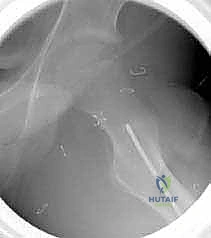

3. إدخال السلك الدليلي (Guide Wire)

تحت توجيه الأشعة السينية المباشرة داخل غرفة العمليات (C-arm)، يقوم الدكتور هطيف بإدخال سلك دليلي في عنق ورأس عظم الفخذ بالزاوية الصحيحة والمحسوبة بدقة.

4. القطع العظمي (The Osteotomy)

باستخدام منشار جراحي دقيق جداً وعالي السرعة، يتم إجراء قطع عرضي في عظم الفخذ في المنطقة المحددة. هذه الخطوة تفصل الجزء العلوي (الرأس والعنق) عن الجزء السفلي (جسم العظم).